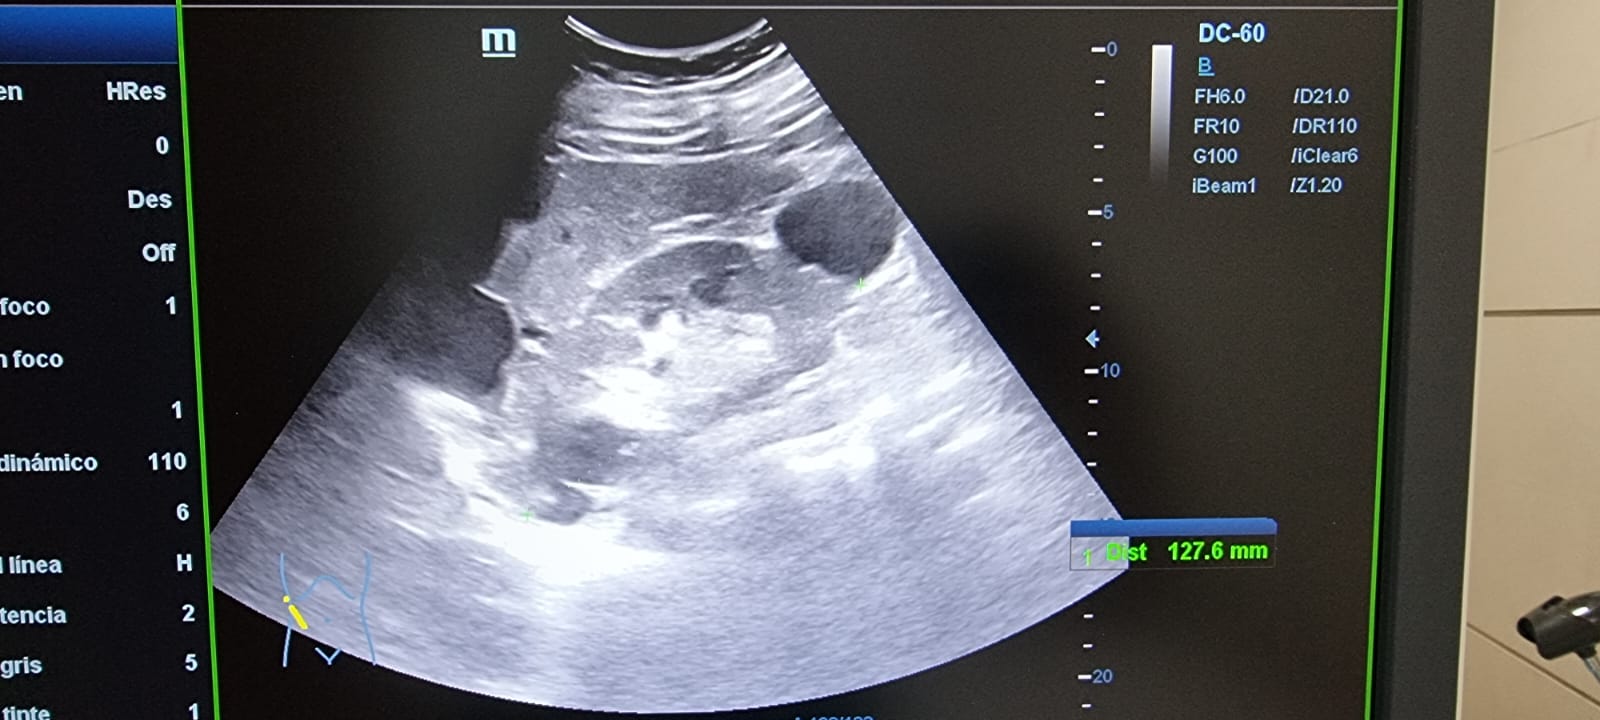

Ecografía abdominal: Hepatomegalia esteatósica difusa leve con múltiples imágenes anecoicas con refuerzo posterior, sin vascularización, compatible con poliquistosis. Riñón derecho con múltiples imágenes anecoicas en polo superior e inferior con refuerzo posterior. Sin signos de uropatía obstructiva. Riñón izquierdo con presencia de múltiples imágenes anecoicas compatibles con poliquistosis.